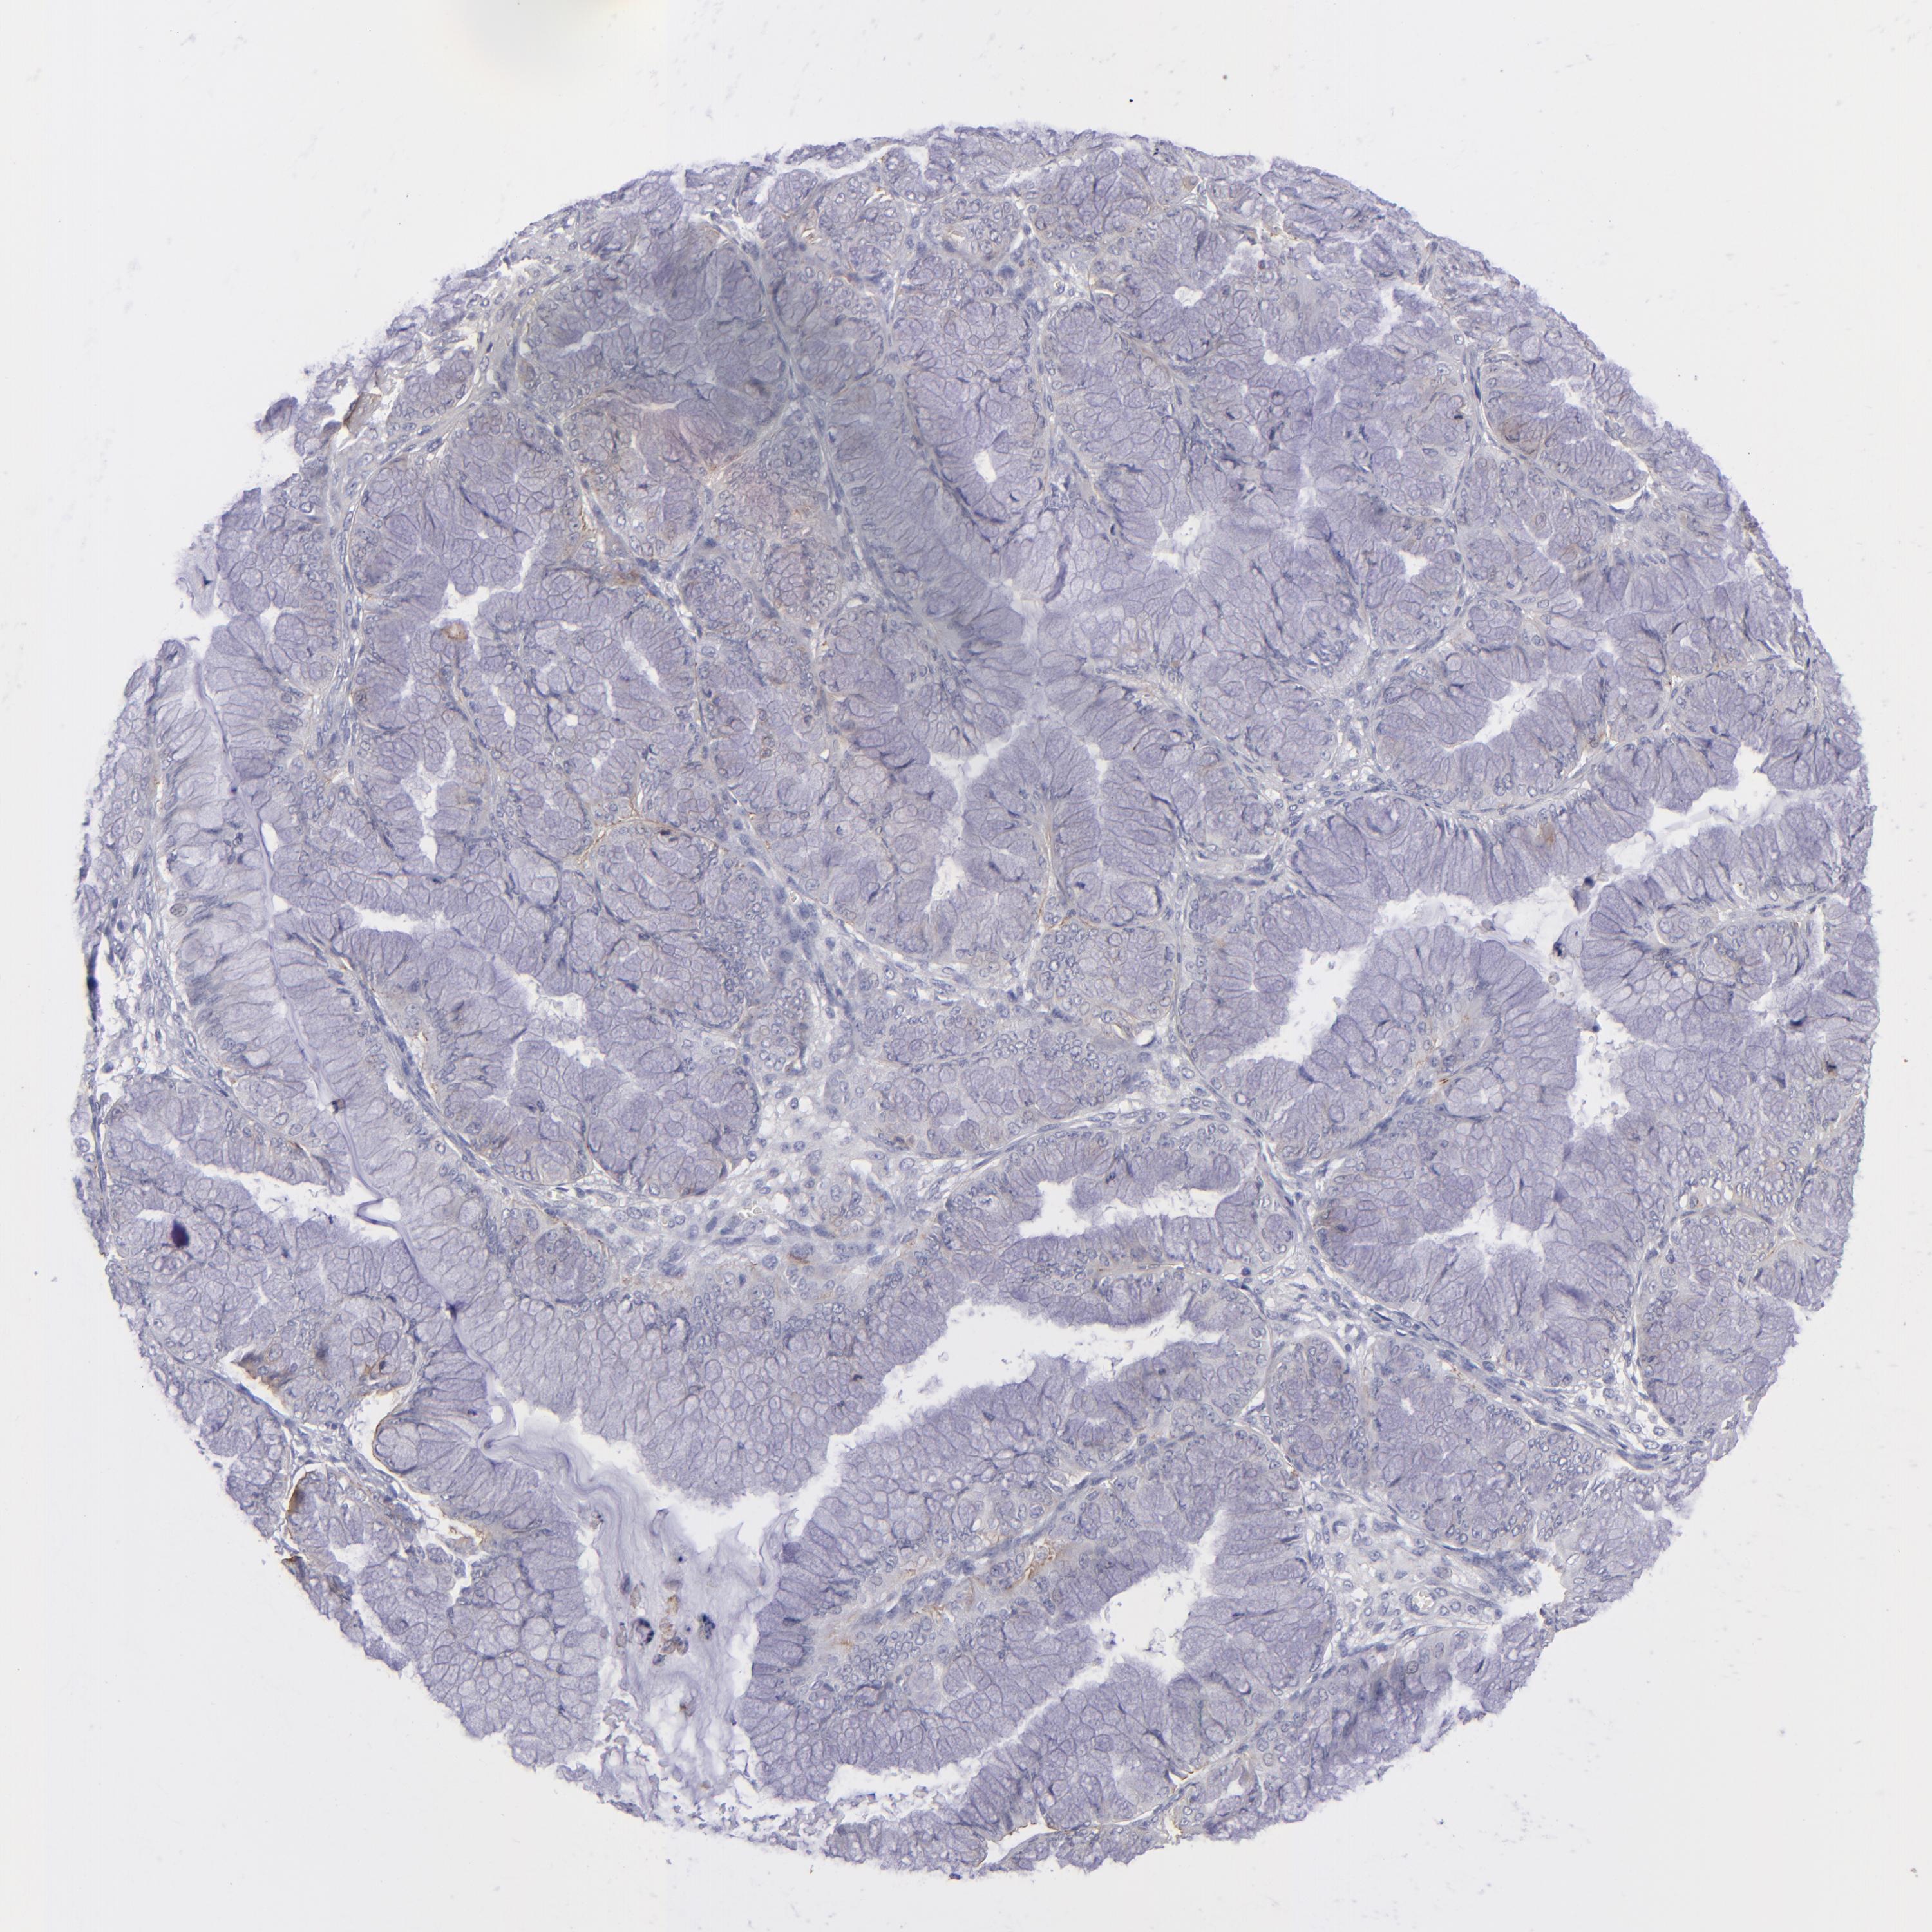

OVARIAN CANCER - Protein expressioni

A mouse-over function shows sample information and annotation data. Click on an image to view it in a full screen mode. Samples can be filtered based on level of antibody staining by selecting one or several of the following categories: high, medium, low and not detected. The assay and annotation is described here.

Note that samples used for immunohistochemistry by the Human Protein Atlas do not correspond to samples in the TCGA dataset.

Antibody stainingi

Antibody staining in the annotated cell types in the current human tissue is reported as not detected, low, medium, or high, based on conventional immunohistochemistry profiling in selected tissues. This score is based on the combination of the staining intensity and fraction of stained cells.

Each image is clickable and will lead to virtual microscopy that enables deeper exploration of all samples and also displays staining intensity scores, fraction scores and subcellular localization as well as patient and tissue information for each sample.

Antibody HPA036348

Antibody HPA036349

Antibody CAB002422

Antibody CAB005258

Cystadenocarcinoma, serous, NOS

Carcinoma, NOS

Cystadenocarcinoma, mucinous, NOS

Carcinoma, endometroid